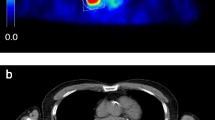

Image analysis (calculation of SAM)

A volume of interest (VOI1) was drawn using PMOD software over the primary tumour lesions of patients of substudy 1 on all reconstructed image sets (1- to 10-min reconstructed images) as well as over all individual metastatic liver lesions of patients of substudy 2 (scan 1 and scan 2). A second VOI (VOI2) was delineated around VOI1 directed to a small zone of homogeneous background. The borders of VOI1 were set at a reasonable distance from the tumour lesions in order to avoid PVE and to ensure that no spillover from the tumour lesion to VOI2 occurred (see Fig. 1). SAM and normalized SAM values were derived using the formulas described in the phantom study, but without the volume correction for VOI1, as this does not apply on patients. In patients with multiple liver metastases (substudy 2) SAM was calculated as the sum of the individual SAMs of the lesions.

18F-FDG PET scan of a patient with colorectal carcinoma metastasized to the liver. A volume of interest (VOI1, blue VOI) was set at a reasonable distance from the metastatic lesion in order to avoid PVE. A second VOI (VOI2, green VOI) was delineated around VOI1. Subtracting the background activity in VOI2-VOI1 from VOI1 yields SAM